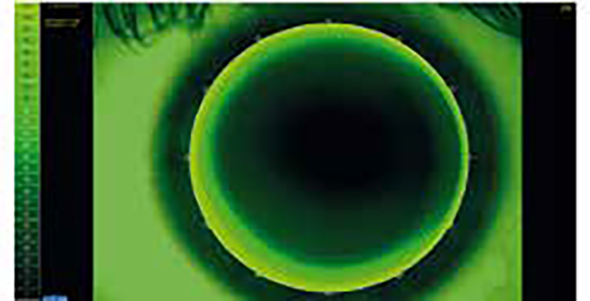

The device is equipped with a white light source for capturing color images or videos, a diffuser filter for analyzing the tear lipid layer, and a cobalt blue light source for assessing rigid contact lens clearance with fluorescein. The magnification adjustment is also particularly useful for capturing images of the tear meniscus and ocular redness